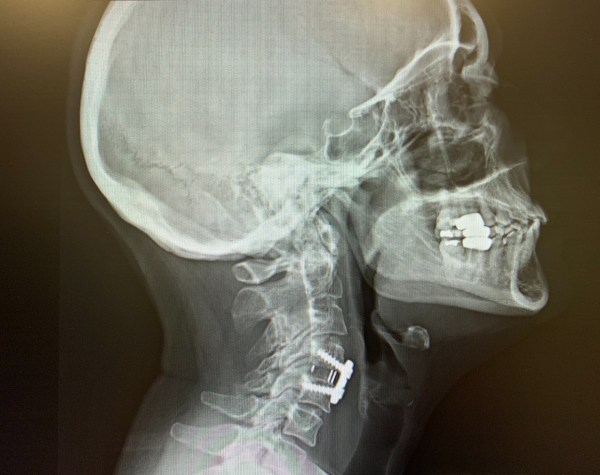

I finally decided to have a cervical surgery for my ongoing neck/shoulder/nerve issues. Over the past 7 years, I had done everything under the sun to get some relief including anti-inflammatories, opioids, muscle relaxers, medical marijuana and CBD, injections, massage, TENS, and physical therapy. Due to my J/RA for almost 50 years, my neck is auto-fused in two places and I have severe degeneration with both spinal and foraminal stenosis resulting in pain, tingling, numbness and nerve damage.

In mid July I had an Anterior Cervical Discectomy and Fusion (ACDF) C4-5. The incision is made from the front of the neck, the affected disc/s are removed and replaced with a spacer, and the surrounding osteophytes are removed. Then a small plate and screws are placed to fuse the level.